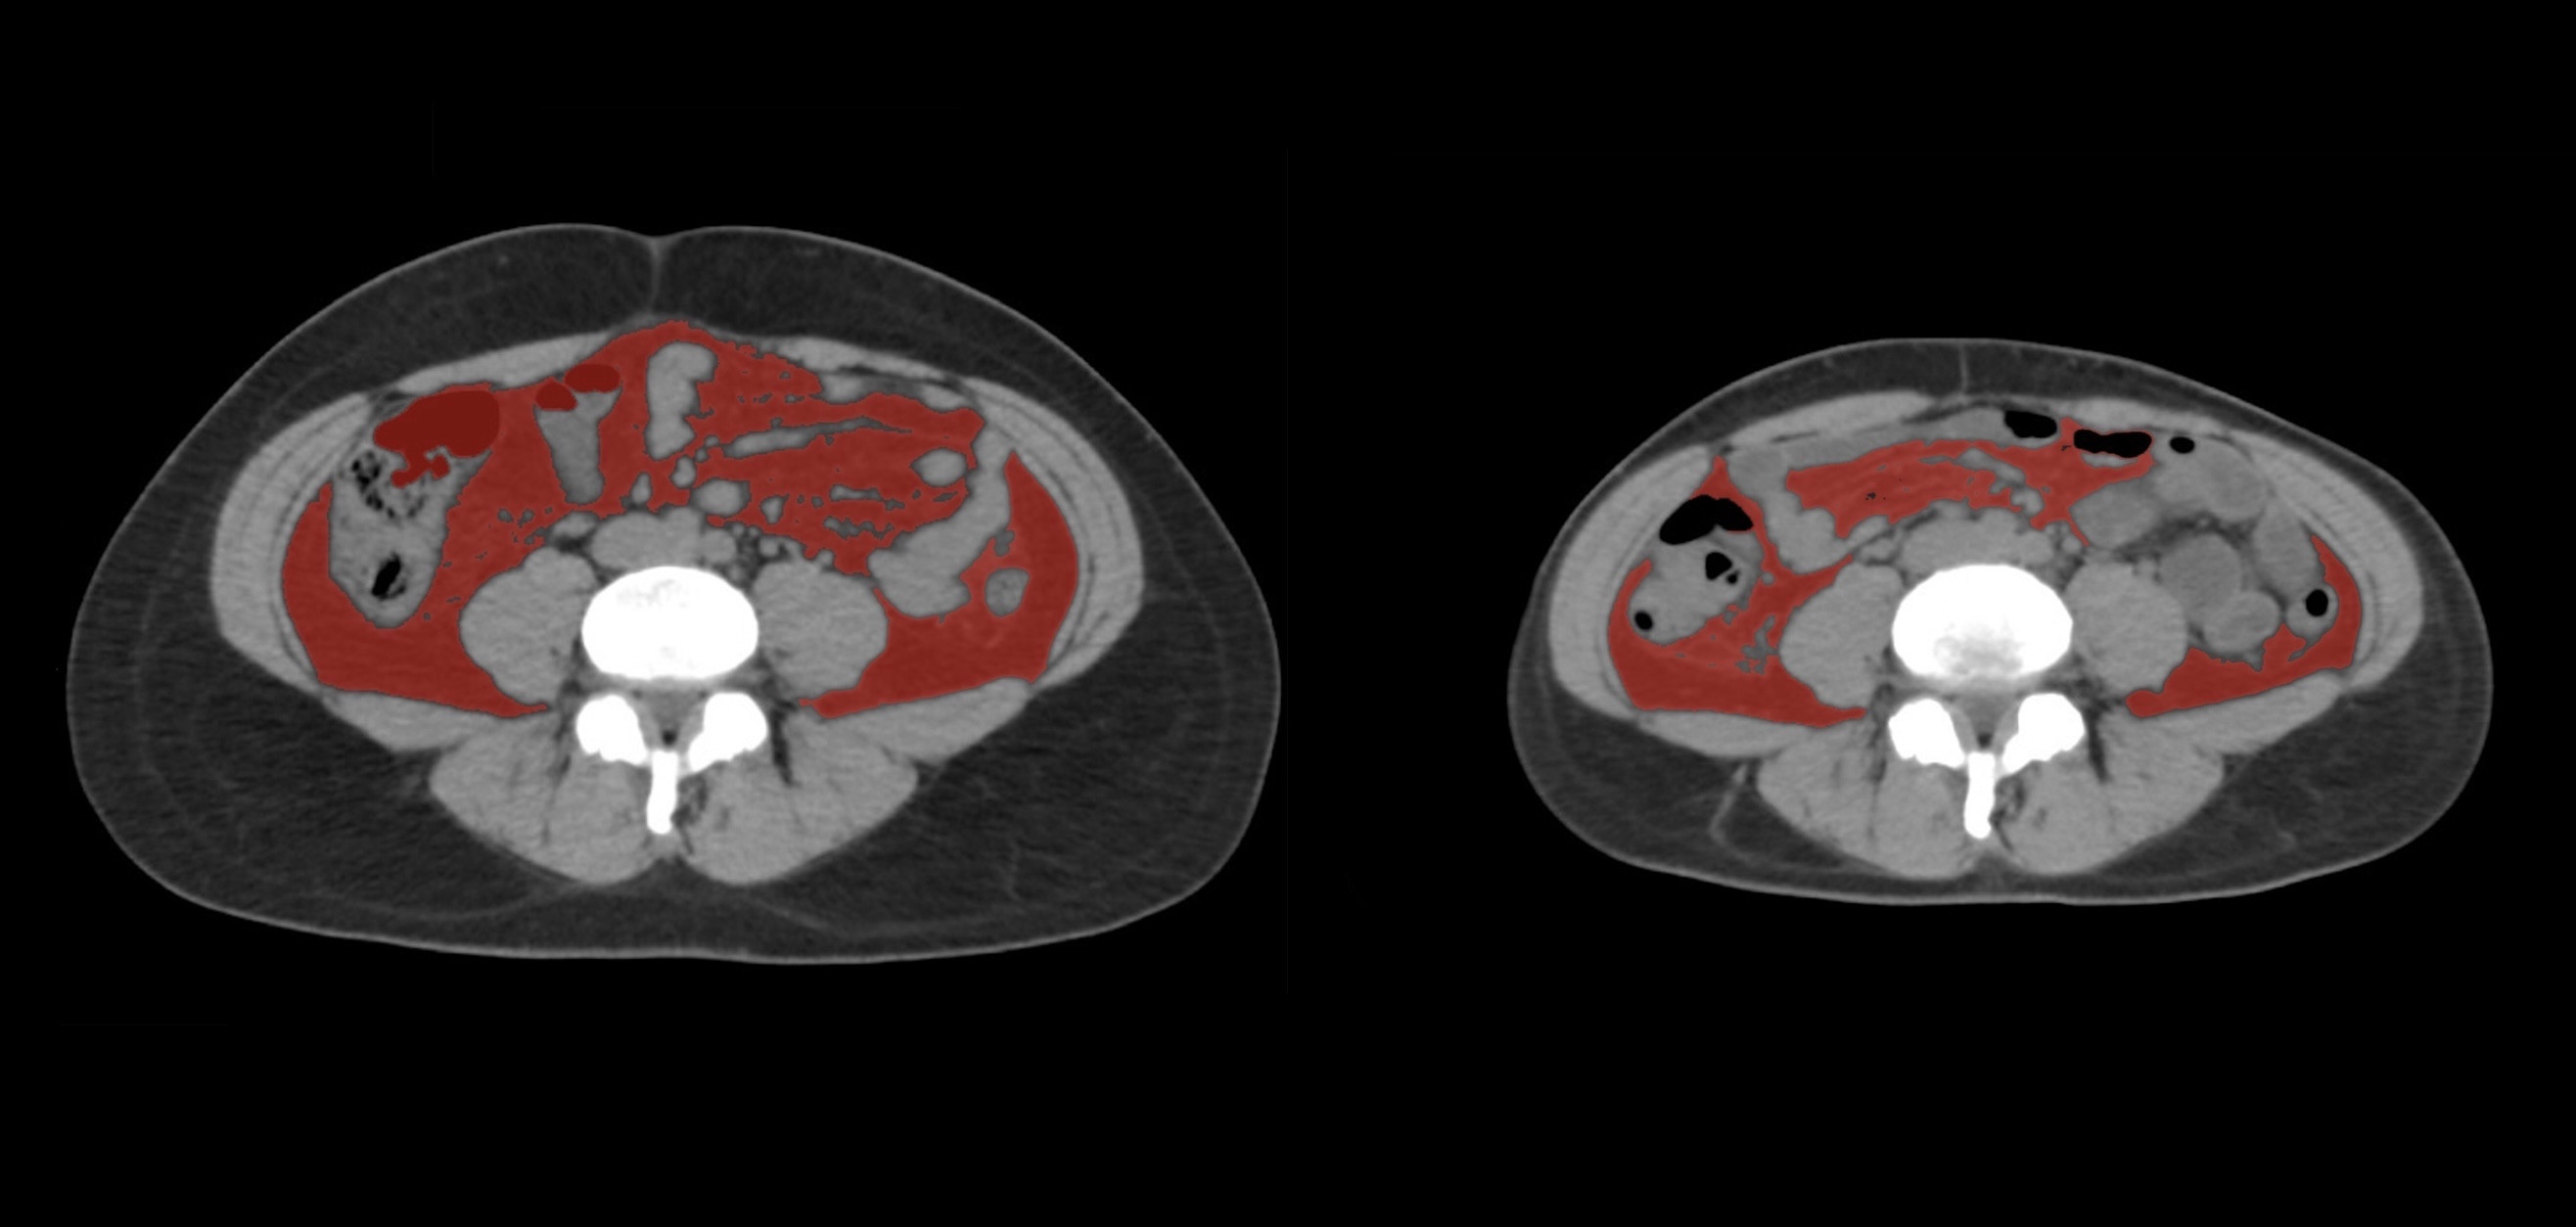

④

50代・男性(ご本人のご厚意で画像提供)

治療内容:チルゼパチド7.5mgの週1回自己注射による脂肪減少と脂肪肝改善

治療期間: 12ヶ月(52週)((用量は2.5mgから開始し最大で15mg。減量効果が得られる必要用量には個人差があります。))

費用:自由診療の場合は9900円(税込)×52(週)=514800円

想定されるリスク・副作用:下記に副作用を記載

※医療広告ガイドラインに準拠して表記

1:脂肪の減少

皮下脂肪の減少(赤色部分)